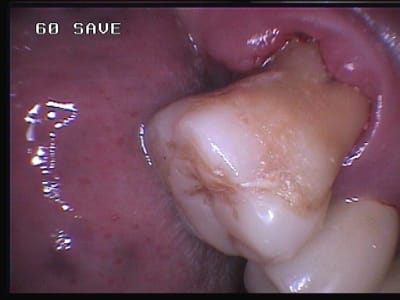

Steph, je suis aussi fou que toi, la preuve:

L'onlay composite 7/8 de la 27 a tenu 9 ans sans problème et la patiente a même mastiqué dessus pendant 5 années alors que la 26 a du être extraite! J'ai du le remplacer en la taillant par un inlaycore lorsque la paroi restante commençait à se carier en palatin et ai réaliser alors enfin un bridge...

L'onlay de la 16 posé en même temps est toujours en place après 14 ans malgré ses parois fines. Où se situent véritablement les limites?

Désolé pour la qualité des photos, mais à cette époque je n'avais que ma vieille caméra endobuccale à fibre optique.

les plâtres ont été conservés comme modèles de montre depuis et m'ont servi à convaincre de nombreux patients de l'intérêt des onlays, comme quoi un brin de folie de temps en temps cela peut faire du bien ;o) ...